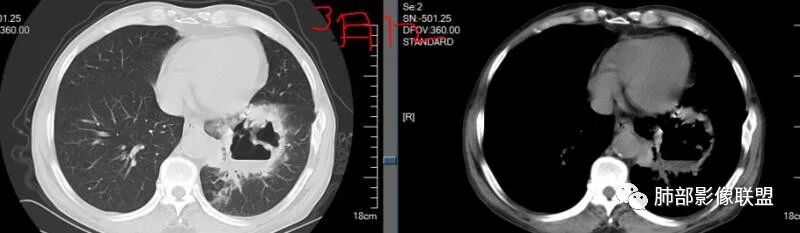

1.老年女性,咳嗽喘息两天入院,没有发热记载。既往糖尿病控制不佳。临床CRP增高,首次实验室白细胞及中性轻度增高。

2.左肺下叶大范围实性密度影,散乱,边界不清,可见液化空洞,病变肺体积轻度增大。支气管相关(相应支气管闭塞)。

1.局限于单肺叶的大范围实性密度影,边界不清,看不出外壁的液化空洞,多符合化脓性感染。

3.金黄色葡萄球菌临床中毒症状明显,常寒颤高热起病,血源性感染者常有皮肤脓肿、伤口感染、蜂窝织炎、化脓性骨髓炎等等。病情变化快,影像进展迅速,短期内(如一两天内)迅速出现的有张力的菲薄气囊影,或多发成串分布的,尤具特征性!较之其他感染,短期内易出现脓胸。本例上述特征似乎不明显。

4.肺炎克雷伯杆菌肺炎病灶也易形成脓腔。本例患者未出现典型金葡感染影像学特征,患者临床表现相对“逍遥”缓慢,结合实验室检查,更符合肺炎克雷伯杆菌肺炎。